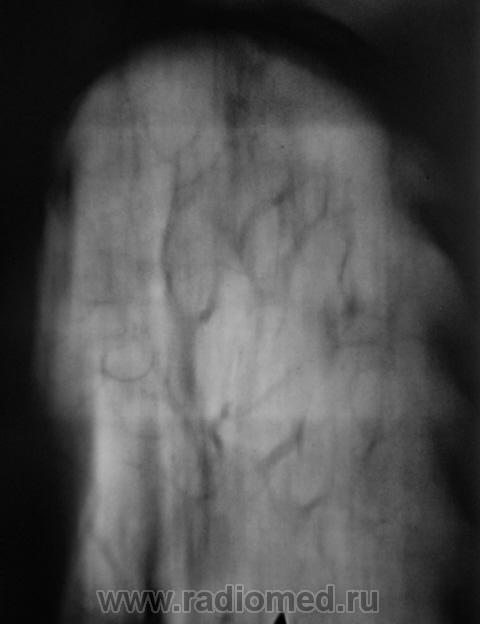

При расшифровке цифровых флюорограмм "пациент взят на контроль". Жалоб пациент не предъявляет. Произведено стандартное дообследование - рентгенография и томография.

Кальцинаты, инуративные очаги в зоне пневмосклероза. Отзвучавший туб. процесс. Больше пока не вижу.

Уважаемый Валентин Львович! Не стал бы торопиться с выводами об " отзвучавшем туберкулезном процессе". Во-первых, без наличия и изучения рентгенархива (при его наличии) делать такие выводы не осмелился бы. Во- вторых, зона пневмосклеротических изменений в легких не соответствует зоне очаговых изменений (гораздо больше!). Создается впечатление о наличии очагов отсева. В общем рентгенконтроль в динамике и консультация фтизиатра. Последнее слово за ними.

В таком случае, Валентин Львович, Вы подтвердили мои сомнения по поводу активности процесса. 2 года назад норма, а теперь такая картина. Это активный процесс. Выраженный пневмосклероз в виде "сетки" в целой доле. Пациента необходимо направить к фтизиатрам.